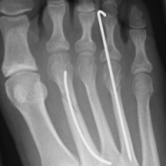

Röntgenbilder